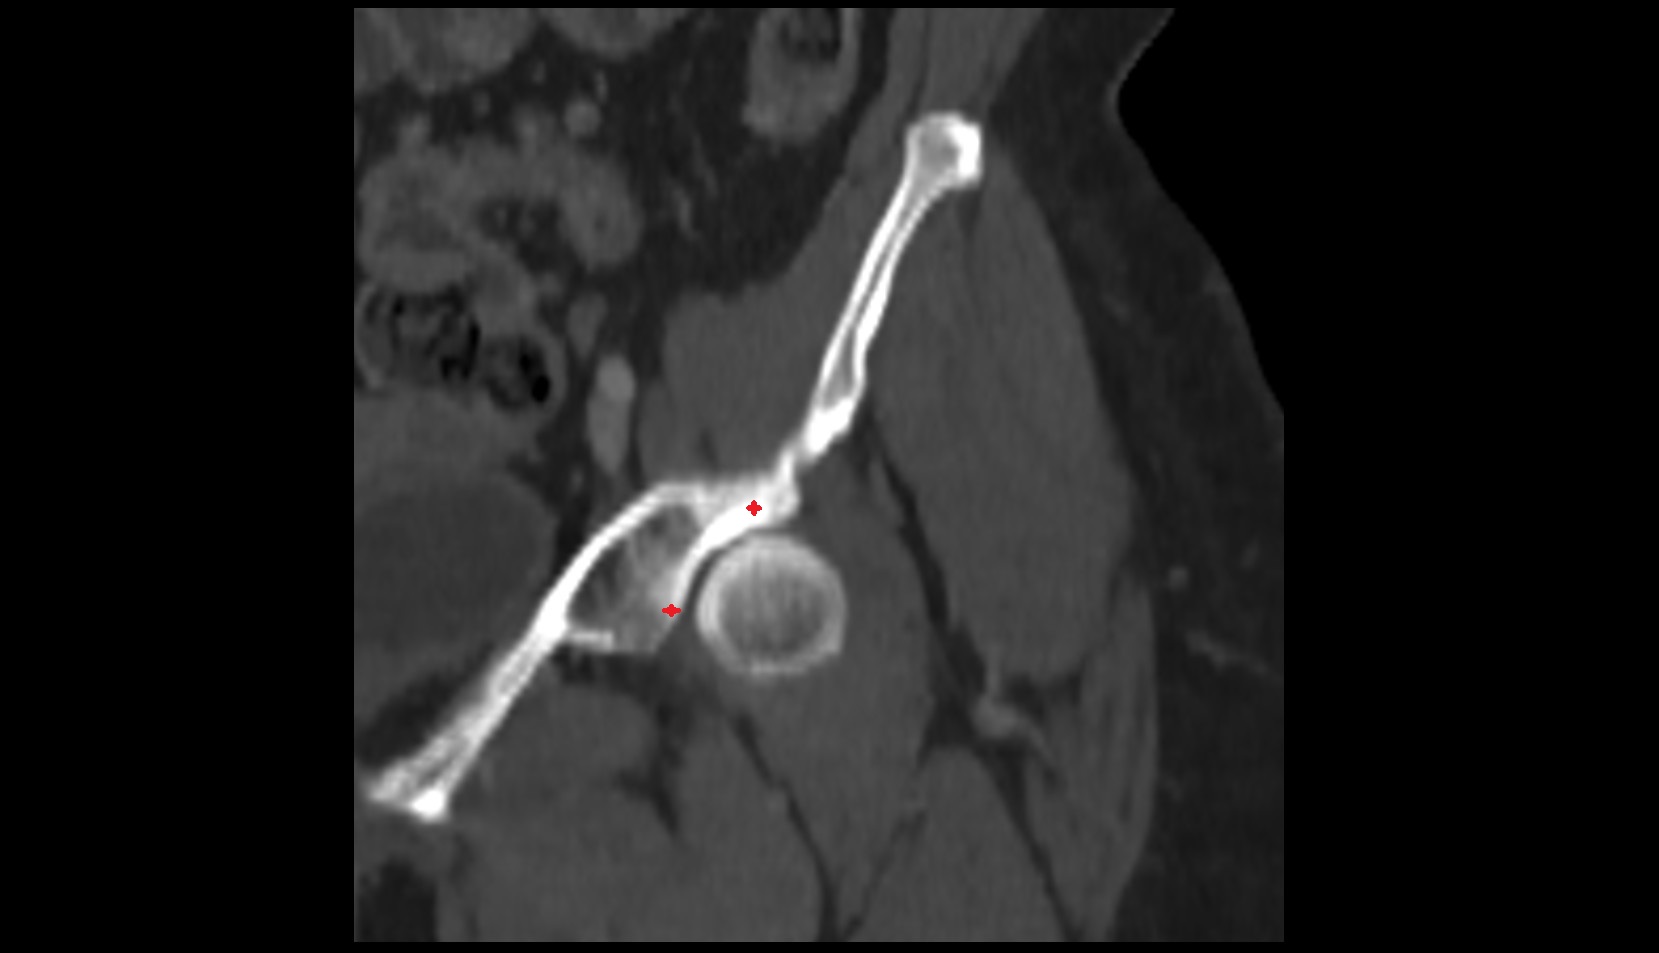

- Femoral artery

- External iliac artery

- Internal iliac artery

- Deep femoral artery (profunda femoris)